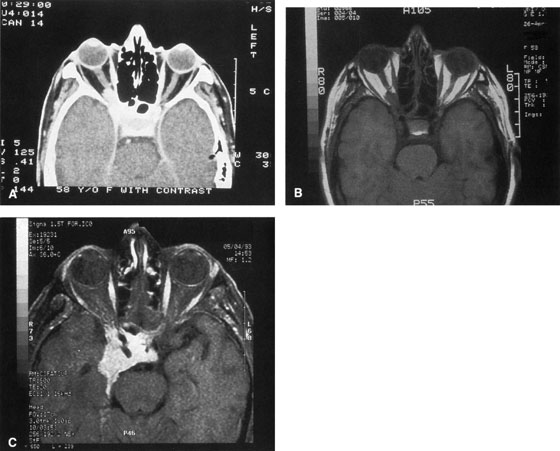

wall still can be carried out. | Fig. 9. A,B. Coronal and axial CT images of a large intraconal neoplasm. C. Because it was felt to represent a well-encapsulated cavernous hemangioma, this

lesion was a candidate for removal via an eyelid crease orbitotomy

without bone removal. The eyelid crease incision marked. D. Incision made with scalpel. E. Orbicularis muscle is tented up and incised to expose the underlying septum. F. Dissection of a skin-muscle flap deep to orbicularis exposes the orbital

septum and superior orbital bony rim. G. Cutting cautery is used to incise periosteum along the superior and lateral

rims; finger palpation of the bone helps to direct this incision. H. Periorbita is elevated along the mesial surface of the lateral orbital

rim in order to expose the deep orbital tissues. I. The cavernous hemangioma is visualized in the wound. Retraction is provided

by one or more malleable retractors. J. Cryoprobe is affixed to the hemangioma to facilitate manipulation of the

lesion. K. Large cavernous hemangioma after removal through the eyelid crease incision

which was accomplished without bone removal. L. Periorbita is reattached over the lateral rim. M. The eyelid crease incision is closed with a running suture. |

always can be extended farther posteriorly if exposure is inadequate.   Figure 10. A. Large, well-encapsulated intraconal mass on MR scan. B. Small lateral canthotomy incision will be used to perform lateral orbitotomy

and remove the intraconal mass.

Figure 10. A. Large, well-encapsulated intraconal mass on MR scan. B. Small lateral canthotomy incision will be used to perform lateral orbitotomy

and remove the intraconal mass.